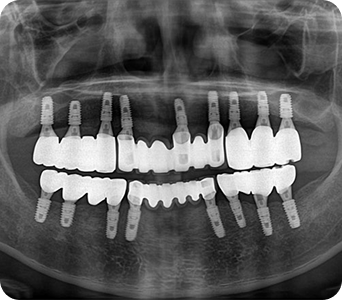

임플란트

임플란트를 했더니 고기가 잘씹혀요!